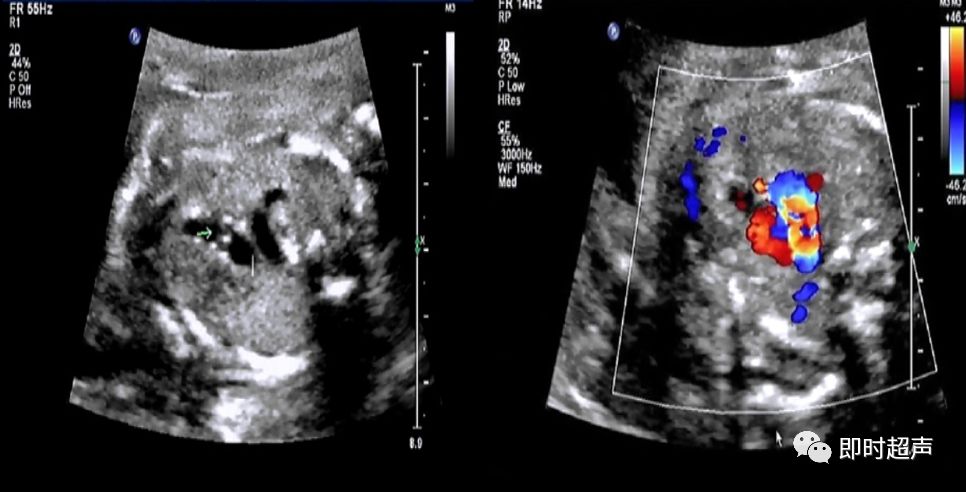

侧动探头连续观察即可观察到动脉导管走形迂曲,但还是汇入降主动脉

动脉导管瘤

胎儿动脉导管瘤的预后

- 动脉导管迂曲扩张和动脉导管瘤对新生儿最常见的影响就是动脉导管未闭。但随着研究的深入,发现动脉导管未闭的发生率并不是很高。

- 但有文献报道,少数动脉导管瘤会发生严重的并发症,甚至导致新生儿死亡。因此,如在产前发现动脉导管瘤或迂曲扩张,应提示临床并追踪。